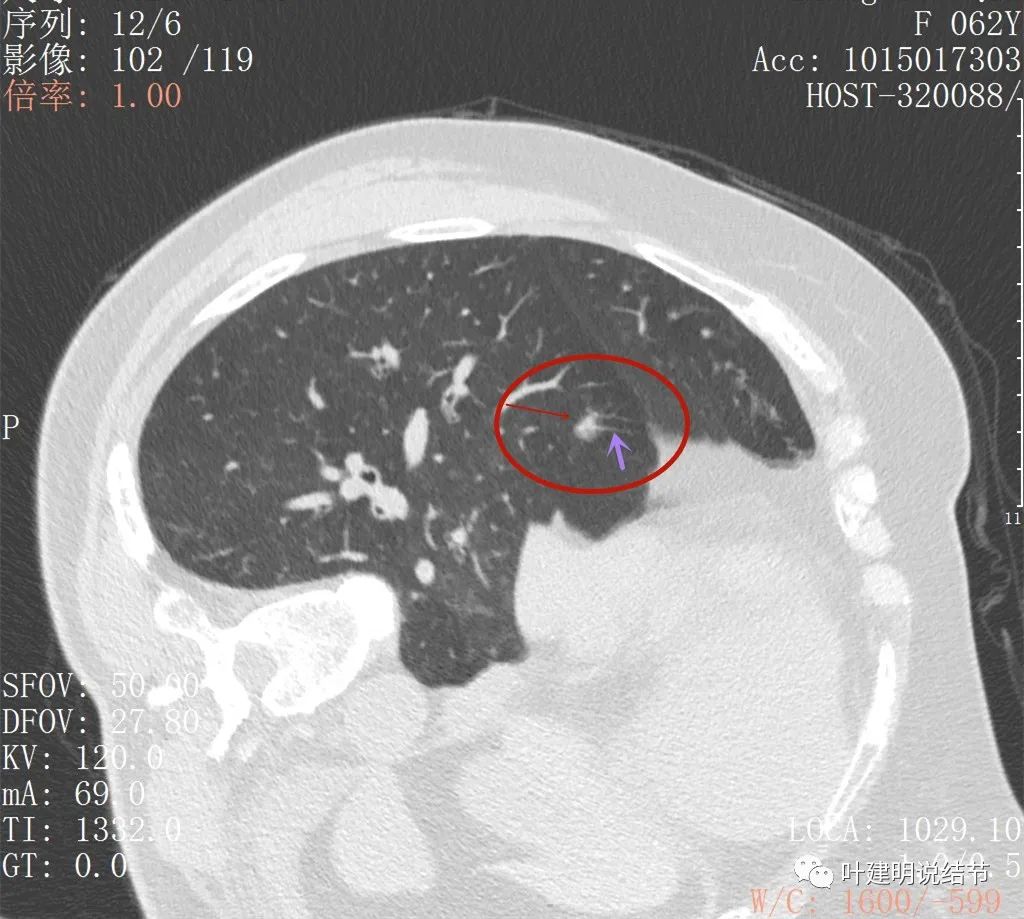

病灶出现,与膈肌间隙欠清

病灶呈实性密度,与膈肌间在此层面上看,并不侵犯或粘连,还是有缝隙的

上图粉色箭头示与膈肌间的缝隙,紫色箭头示病灶有细毛刺征,红色箭头示病灶实性密度